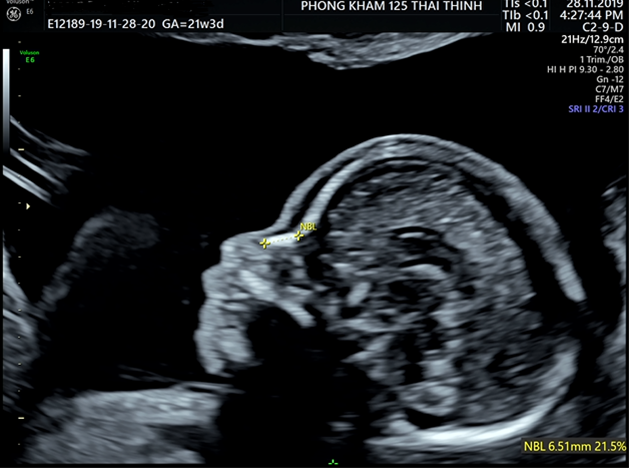

Giai đoạn 2: Đo trong các quý sau của thai kỳ

- Trong các lần siêu âm tiếp theo, các mẹ bầu đều được bác sĩ sẽ thực hiện đo xương mũi của thai. Trong giai đoạn này chiều dài xương mũi khá quan trọng vì không có xương mũi hay xương mũi ngắn đều làm tăng nguy cơ mắc bệnh Down ở thai nhi.

Thiểu sản xương mũi

- Chiều dài xương mũi thấp hơn phân vị 2.5 hoặc 5 so với bảng chuẩn theo tuần thai.

- Nguyên nhân có thể do di truyền, bố mẹ có sống mũi thấp, người châu Á có mũi ngắn hơn, thai nhi phát triển chậm tạm thời,....

| 19 - 20 | 5.0 - 7.0 mm (trung bình 6.75mm) | Số liệu ở thai nhi Việt Nam từ 19- 26 tuần |